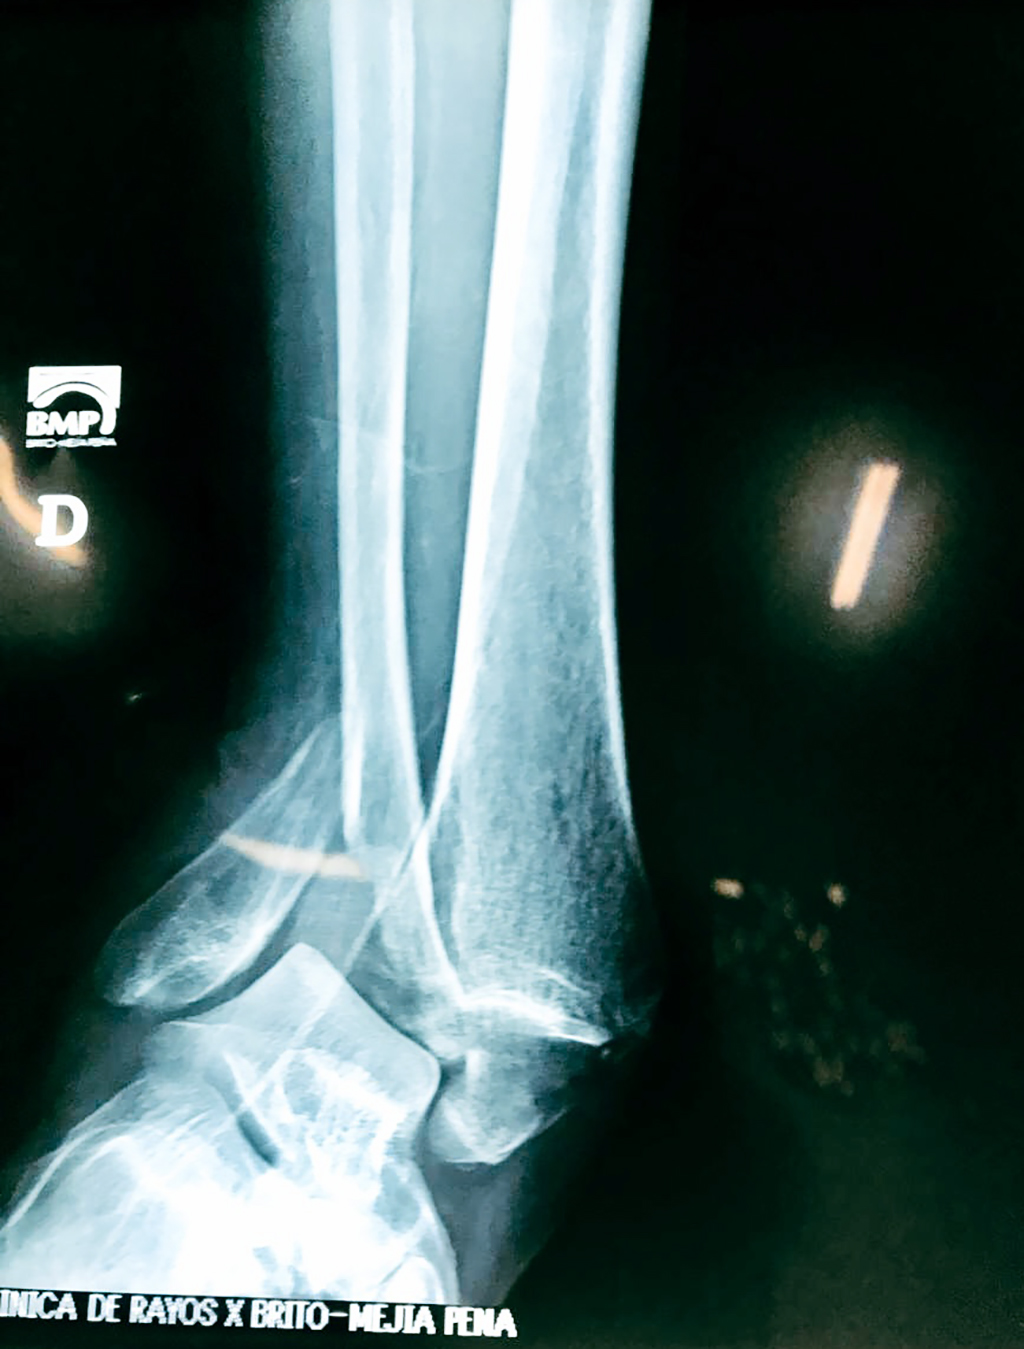

Una fractura de tobillo es la rotura de uno o más de los huesos del tobillo. Estas fracturas pueden ser:

Algunas fracturas de tobillo pueden requerir cirugía si:

- Los extremos de los huesos están desalineados entre sí (desplazados).

- Los tendones o ligamentos (tejidos que sujetan los músculos y los huesos entre sí) están rotos.

Cuando se necesita cirugía, es probable que esta implique el uso de clavijas de metal, tornillos o placas para sostener los huesos en su lugar mientras la fractura se consolida. Los elementos de soporte pueden ser temporales o permanentes.